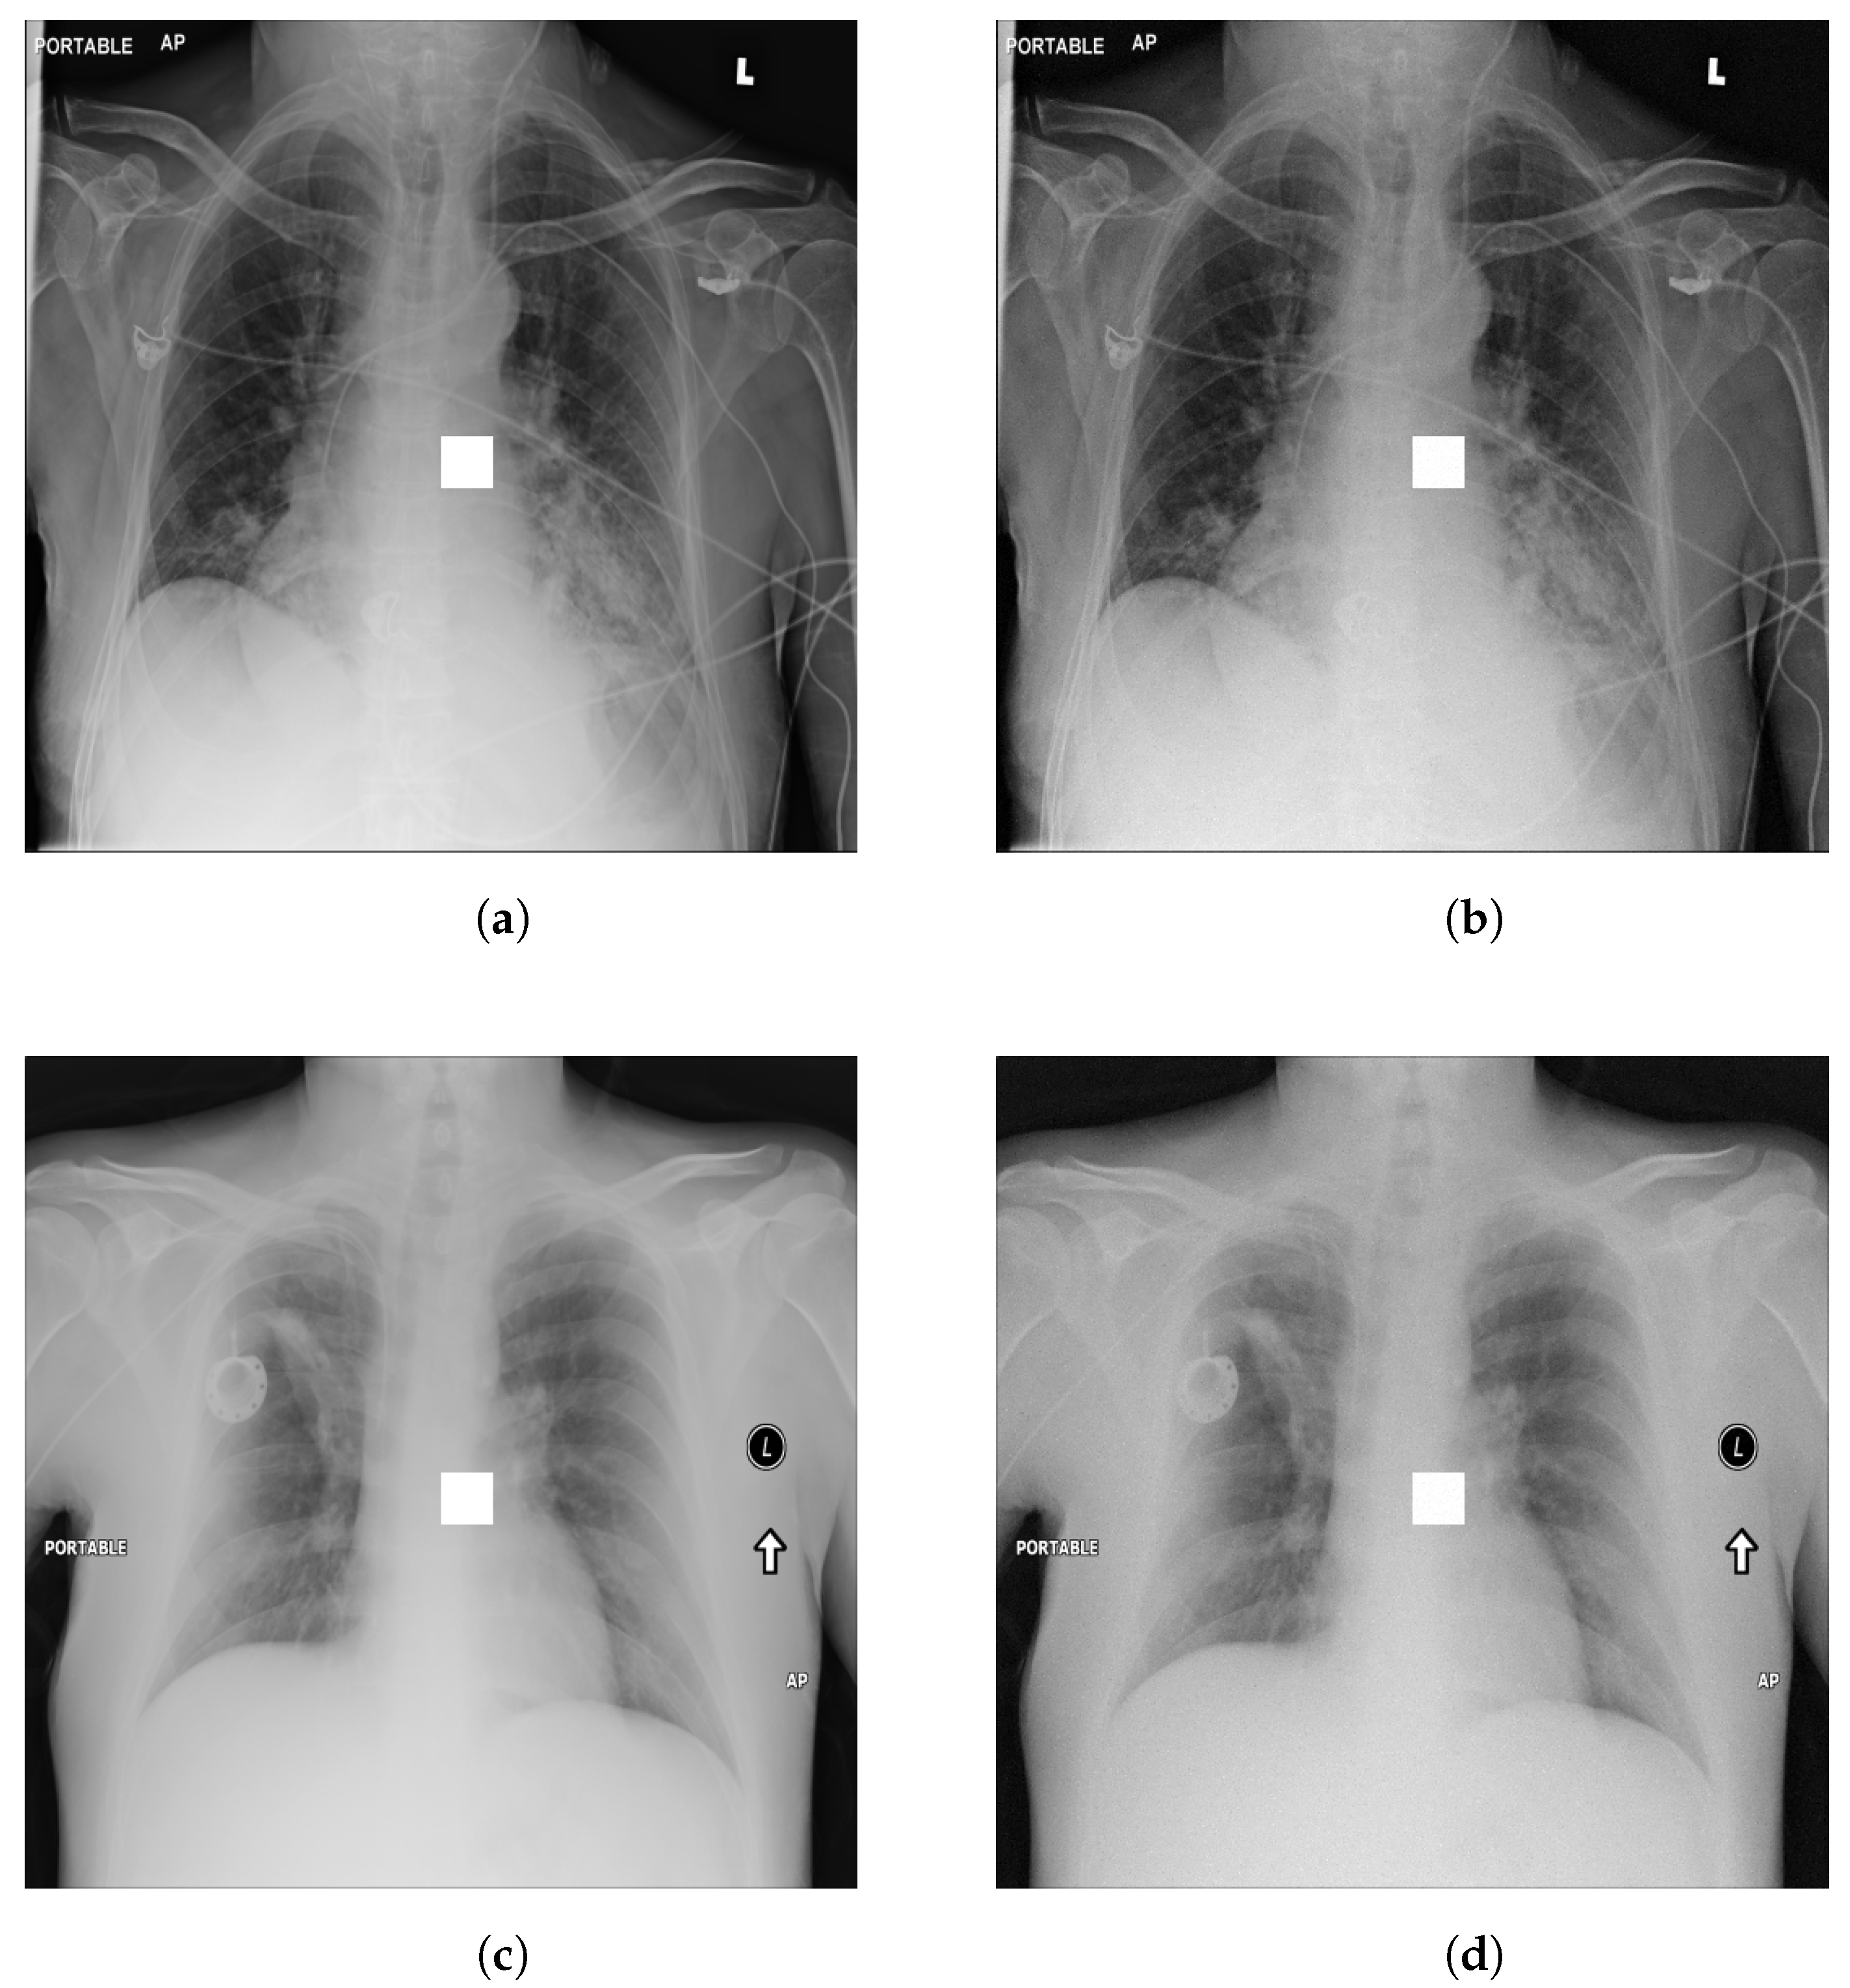

4.1. -LDP-Processed CXR Images

4.2. Qualitative Assessment of LDP-Processed CXR Images